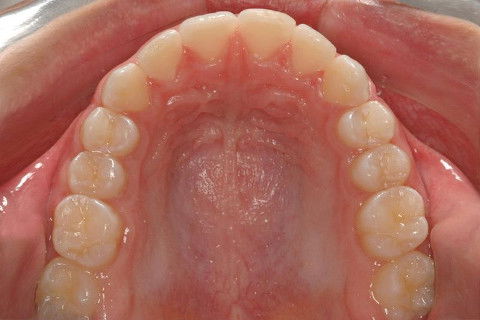

OCLUSAL SUP. FINAL

OCLUSAL SUP. INICIAL